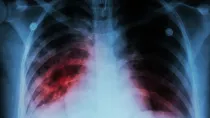

Dlaczego gruźlica nie zniknęła mimo postępów medycyny

Historia nauczycielki z Mrągowa, która tygodniami szukała przyczyny uporczywego kaszlu, odsłania niewygodną prawdę: gruźlica, choć rzadziej widoczna w statystykach niż choroby cywilizacyjne, pozostaje jedną z najbardziej uporczywych infekcji na świecie. Według WHO wciąż jest najbardziej zabójczą chorobą zakaźną na świecie.